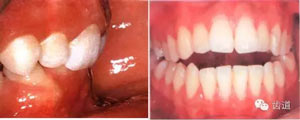

74.jpg

2)、正鎖合與反鎖合:后牙頰舌向錯(cuò)位嚴(yán)重,咬合時(shí)無(wú)合面接觸。

正鎖合:上頜牙舌面與下頜牙頰面接觸。

反鎖合:上頜牙頰面與下頜牙舌面接觸。